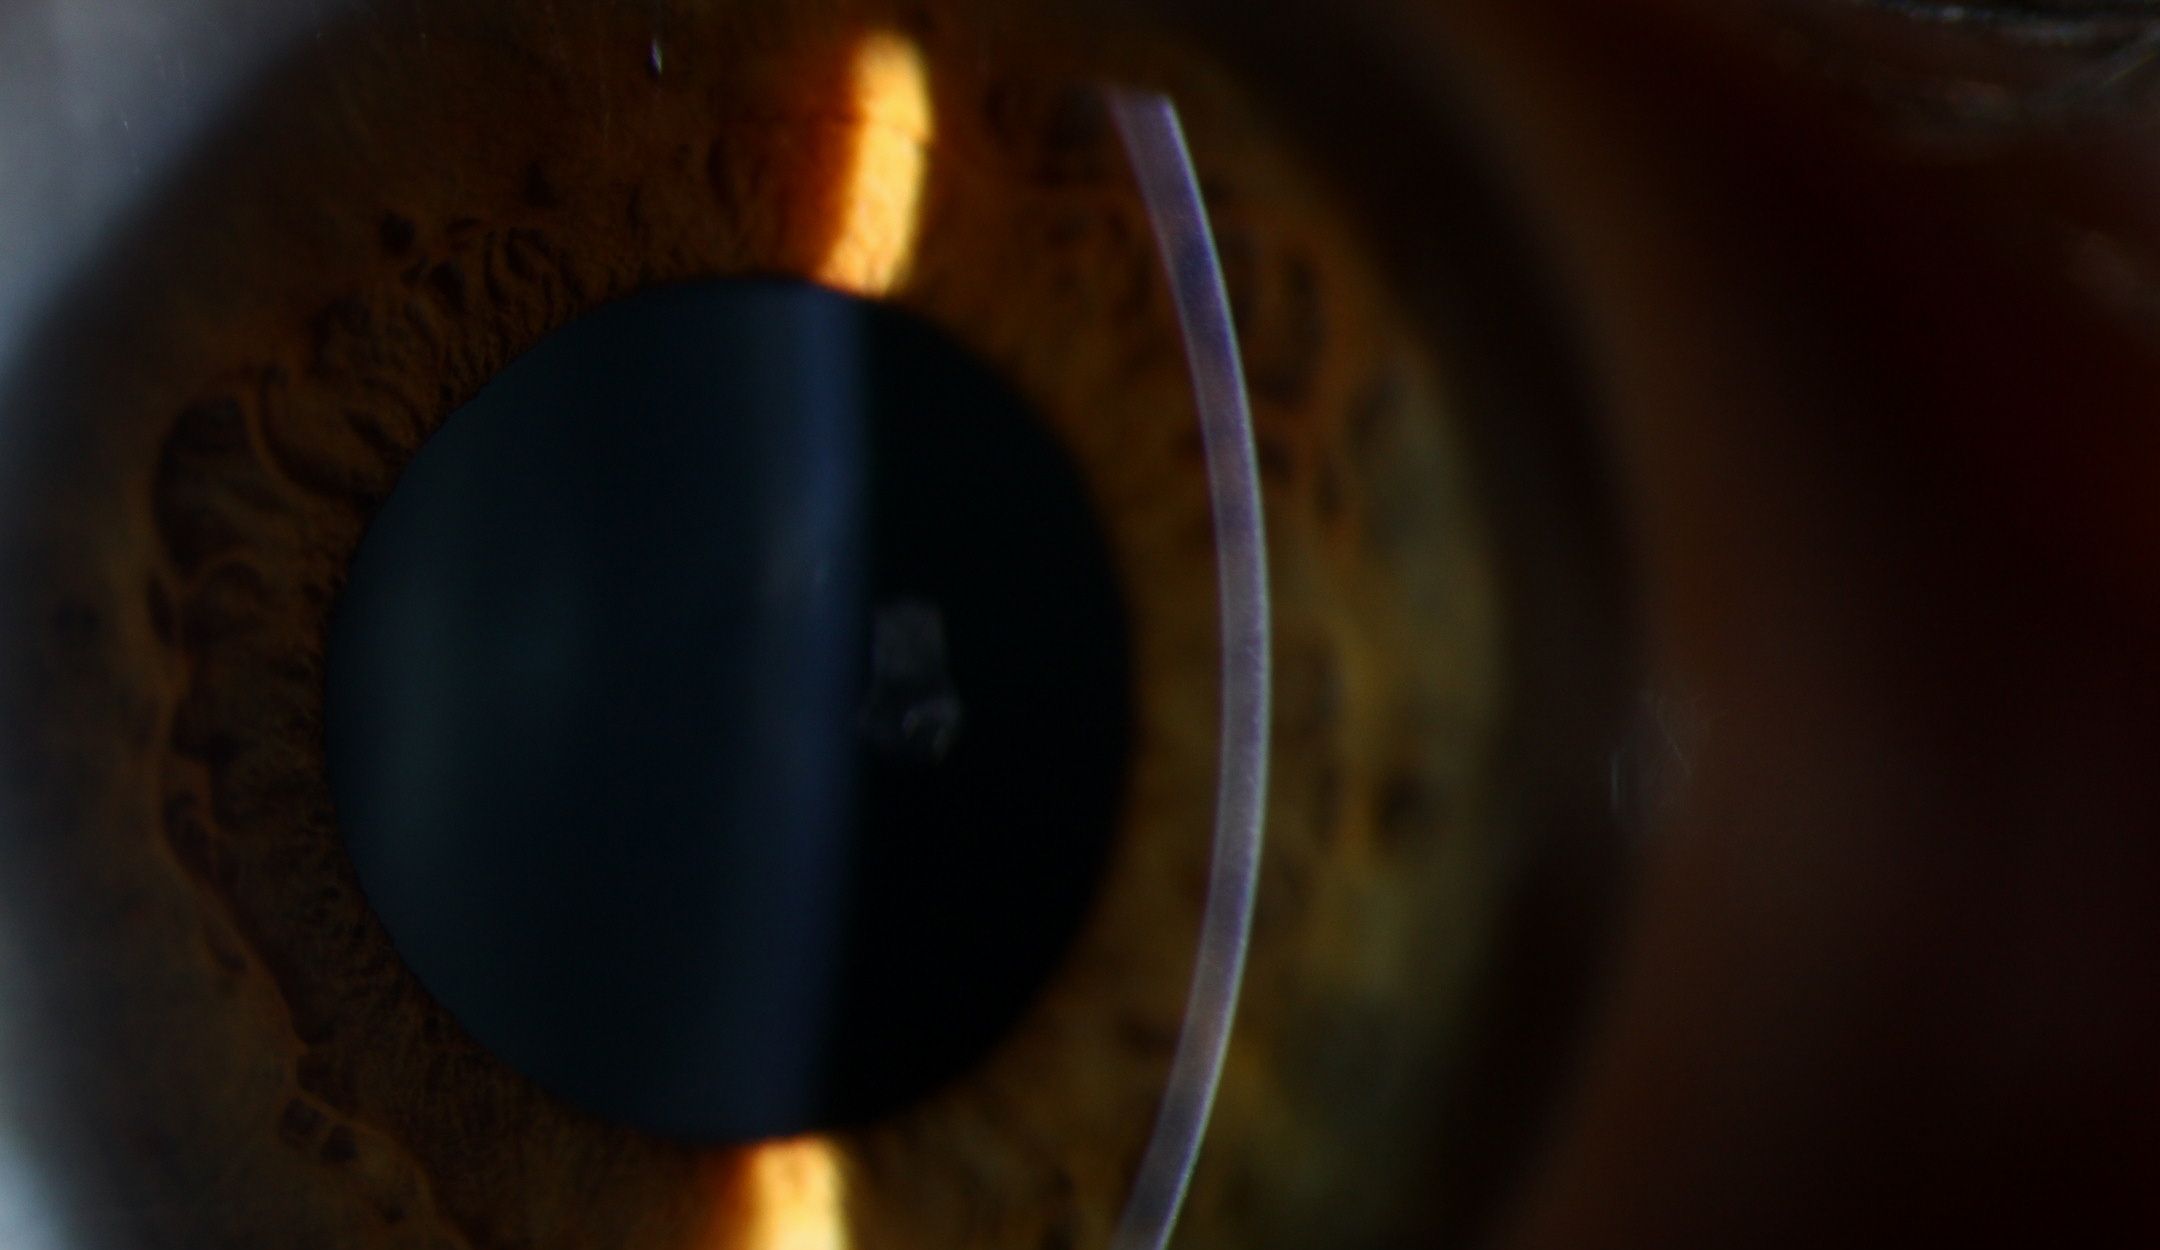

Cataract Surgery

From standard cataract removal to advanced lens-based surgery, backed by a 3,000+ case published ReLACS study. Over 100,000 procedures performed by board-certified surgeons, with in-house diagnostics and a complete care pathway under one roof.